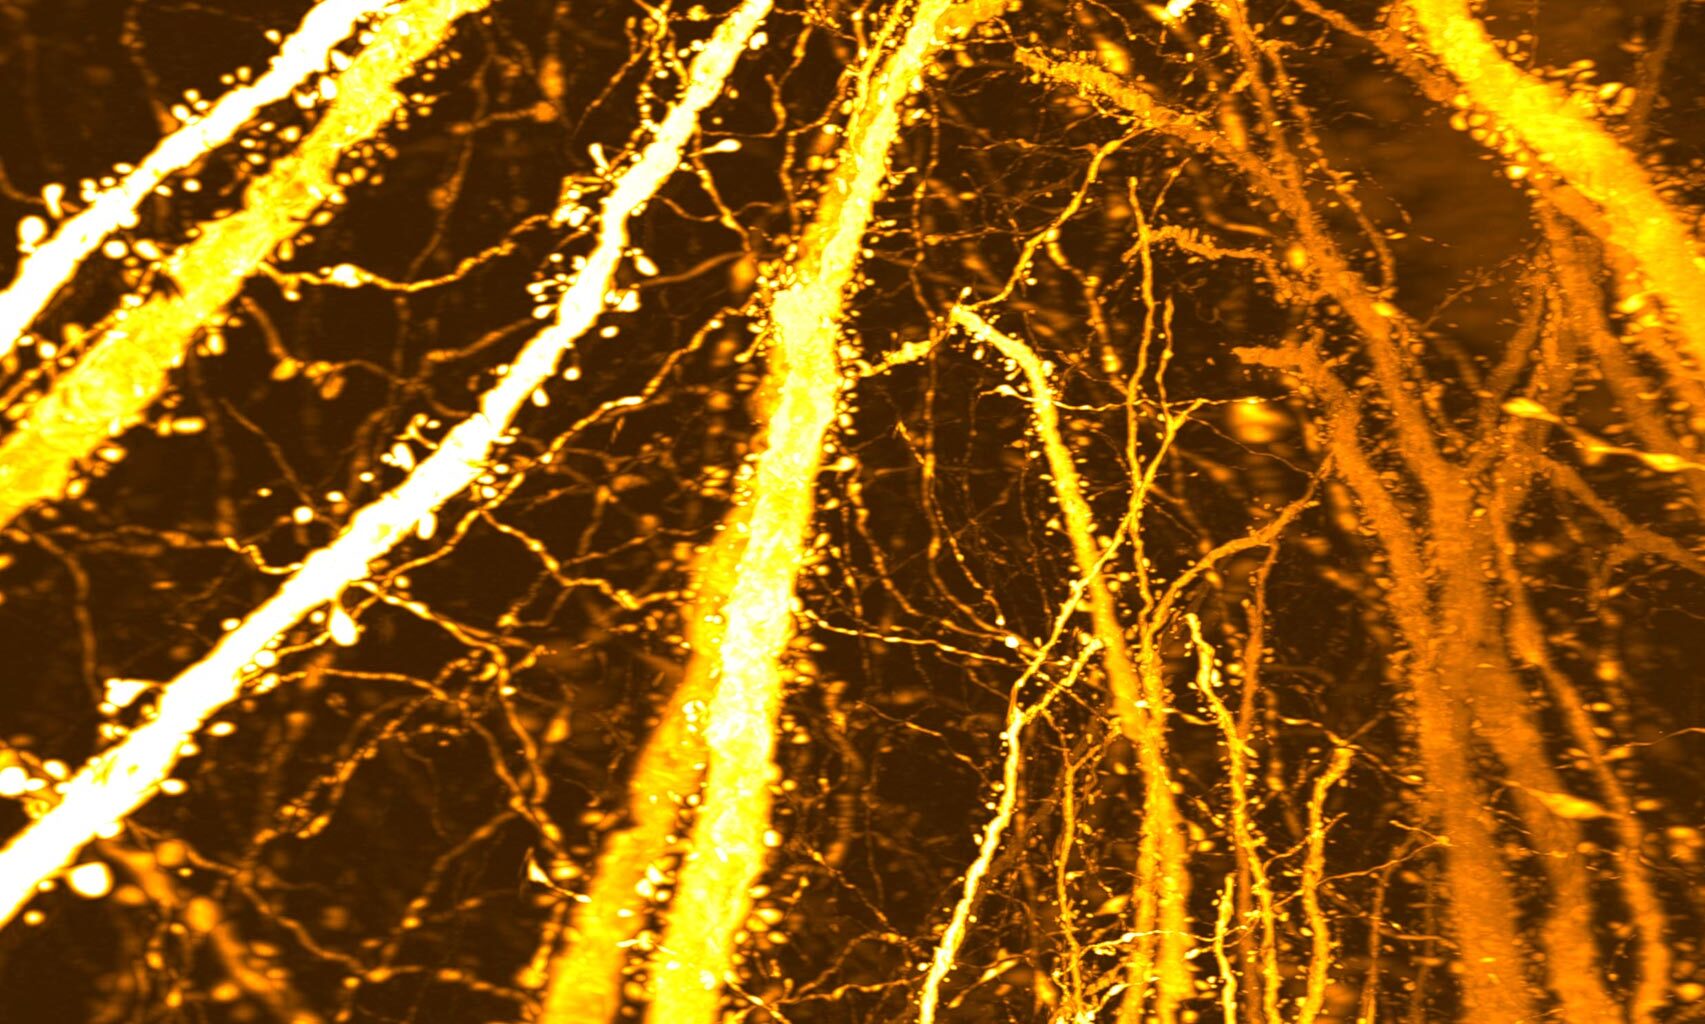

New Synaptic Formation Adolescent BrainThis image shows densely accumulated dendritic spines. Researchers from Kyushu University discovered a previously unrecognized synaptic “hotspot” that forms during adolescence, challenging the long-held view that adolescent brain development is driven mainly by synaptic pruning. Credit: Takeshi Imai / Kyushu University

“We did not set out to study brain disorders,” says Professor Takeshi Imai at Kyushu University’s Faculty of Medical Sciences. “After developing a high-resolution tool for synaptic analysis in 2016, we looked at the mouse cerebral cortex out of curiosity. Beyond seeing the beauty of the neuronal structure, we were surprised to discover a previously unknown high-density hotspot of dendritic spines, the tiny protrusions in dendrites where excitatory synapses are formed.”

Using this method, the team created a complete map of dendritic spines across individual Layer 5 neurons. Their analysis uncovered an unexpected region of extremely high spine density located along the apical dendrite. Further comparisons across developmental stages showed that this dense cluster does not appear early in life but instead emerges specifically during adolescence.

To determine how and when this dense region forms, the researchers followed changes in dendritic spine distribution over time. In mice that were two weeks old and had not yet been weaned, spines were spread fairly evenly along the dendrites. However, between three and eight weeks of age, a period that spans early development through adolescence, spine numbers increased sharply in one specific section of the apical dendrite. Over time, this selective growth led to the formation of a concentrated synaptic hotspot.